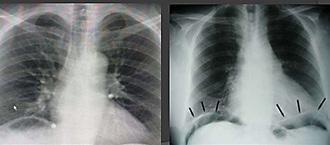

La segunda complicación más común de la úlcera péptica

Las úlceras gástricas prepilóricas → son la causa más común de perforación.

Las úlceras duodenales de la pared anterior tienen más probabilidades de perforarse que las úlceras de la pared posterior (ENARM 2007)

Clínica → dolor súbito, severo y rigidez abdominal (rebote +) repentinos y difusos (ENARM 2017)

(ENARM 2015) (ENARM 2014) (ENARM 2018), signo Jobert + (desaparición de matidez hepática)(ESSALUD 2010)

Confirma → radiografía simple toraco abdominal en bipedestación (ENARM 2017) (ENARM 2015)

(ENARM 2014) (ENARM 2007)

Signos de Neumoperitoneo:

Figura 90. Signo de Jobert → desaparición de la matidez hepática → neumoperitoneo

♦ Signo de Popper

♦ Singo de alas de gaviota

♦ Observación del ligamento falciforme (El aire libre puede delinear el ligamento falciforme)

Tratamiento → cirugía de emergencia

♦ Parche de Graham: reparación quirúrgica de una úlcera duodenal perforada pequeña (generalmente <5 mm) utilizando un trozo de epiplón para cerrar la perforación

A B C D

Figura 91. Signos radiológicos de neumoperitoneo Figura 92.